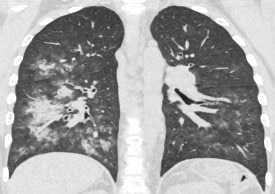

1882. У пациента 14 лет диагноз «лимфома ходжкина», «нодулярный склероз», при выполнении компьютерной томографии определяются участки инфильтрации в правом легком и нижней доле левого легкого, рентгенологическая картина соответствует